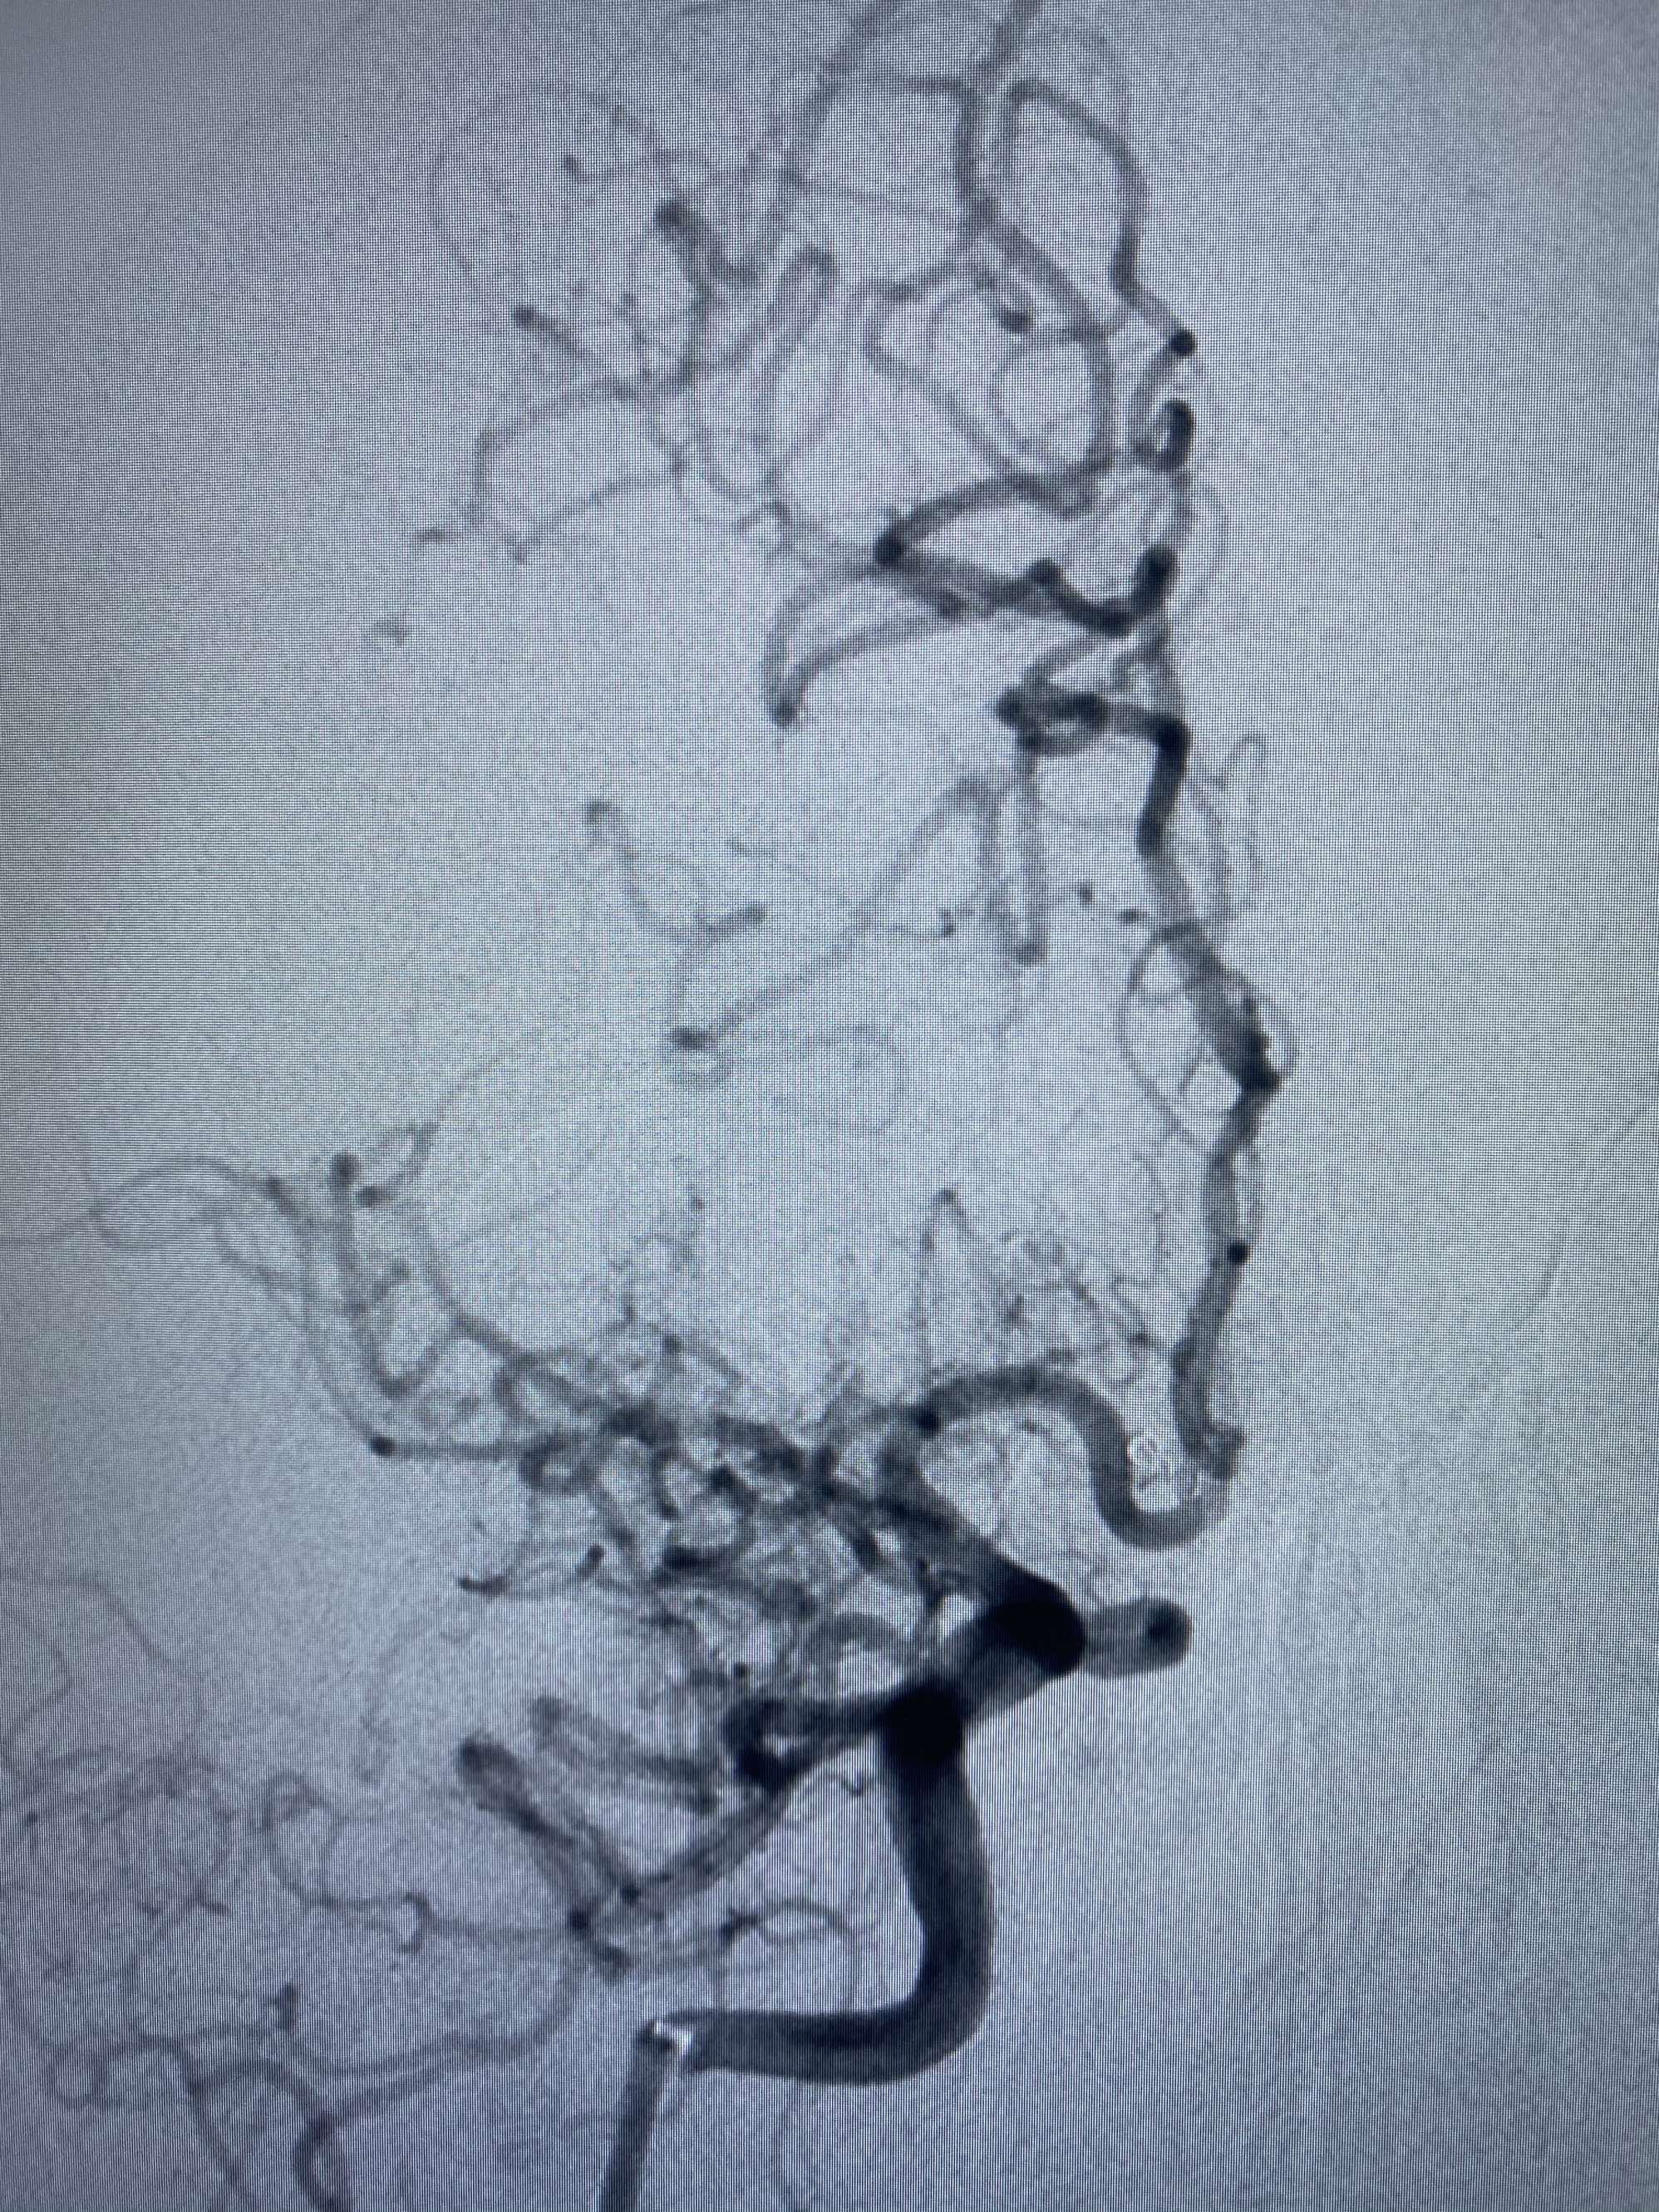

MLS,M79Y,sah,双侧MCA烟雾病,Heubner返动脉瘤,前交通段开窗,细支发出Heubner返动脉,瘤颈细长,瘤颈口比微导管细,弹簧圈2mmx3cm“隔山打牛”填塞治愈,Heubner返动脉保留。

Heubner返动脉是由大脑前动脉A1末端发出的豆纹动脉,由于走形和A1段相反,故称Heubner返动脉,该动脉梗塞可能引起尾状核头梗塞,引起偏瘫和面瘫,便身震颤等症状。